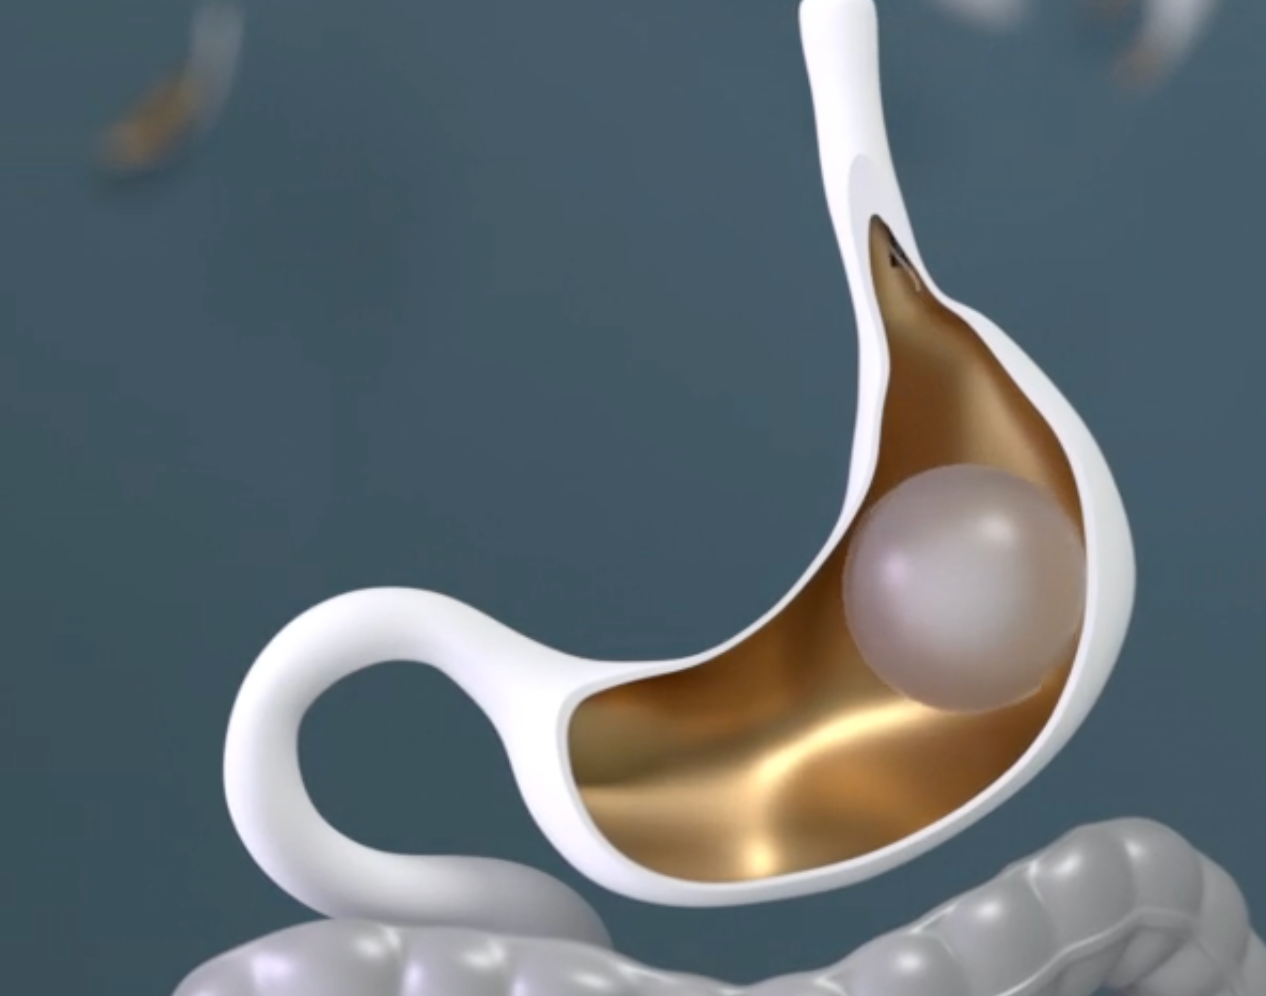

Descubre la eficacia comprobada del procedimiento de balón gástrico para perder peso y cómo puede impulsar tu camino hacia un estilo de vida más saludable.

Compara 5 tipos de balón gástrico, cómo funcionan y cuál se adapta mejor a tus metas de peso. Descubre qué esperar y cómo elegir bien.

¿Qué esperar antes y después del balón gástrico? Descubre cómo funciona este procedimiento no quirúrgico y los resultados típicos de pérdida de peso.

¿Resultados del balón gástrico a 6 meses? Descubre qué esperar y cómo este método no invasivo puede ayudarte a perder peso.